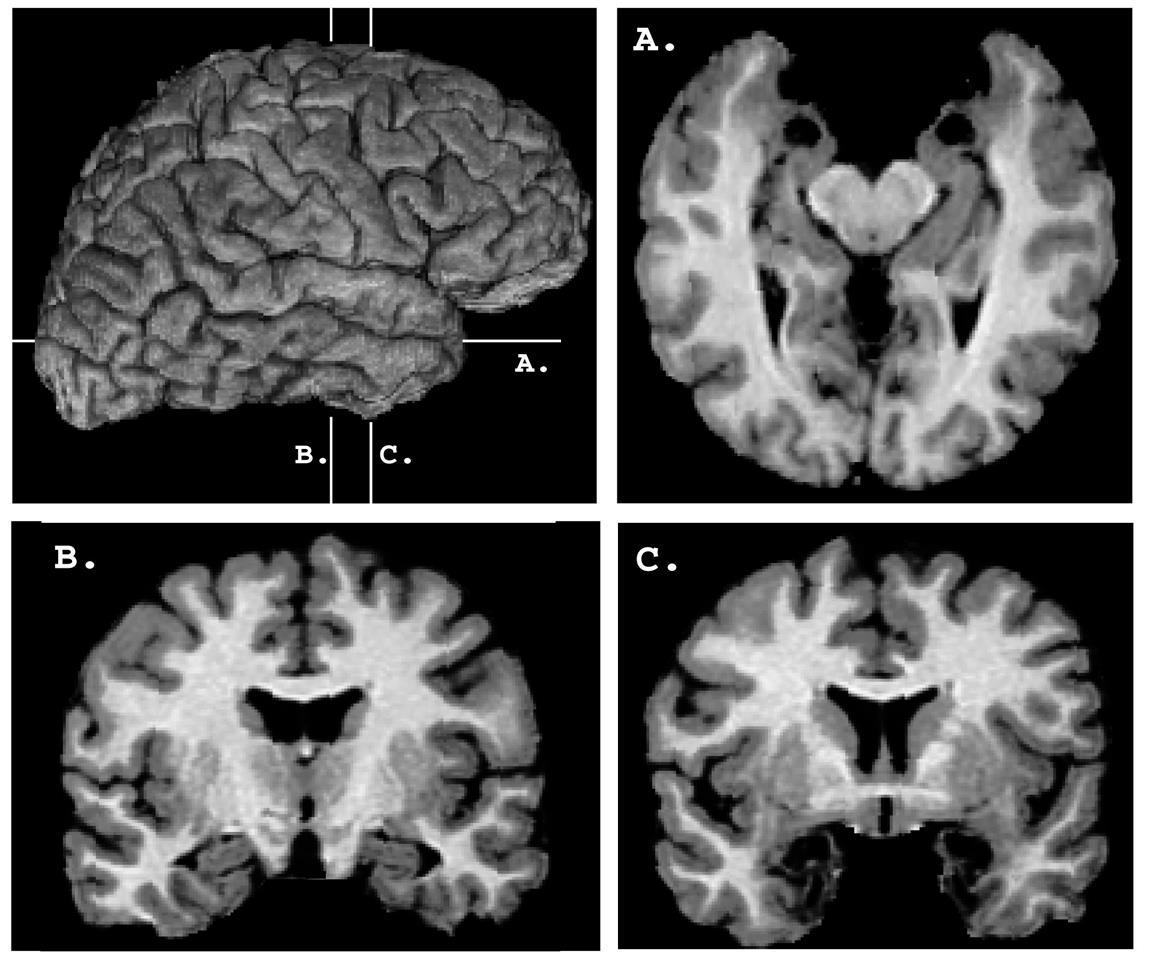

-Hay una paciente que ha sido estudiada intensamente en el laboratorio; se trata de S.M. que tiene ambas amígdalas calcificadas. Su lesión apareció probablemente por primera vez a los 10 años (Feinstein et al., 2011). Descrita por primera vez en 1994 por Adolphs et al. (1994), se le comparó con 12 sujetos con daño cerebral en otras regiones; también se la comparó con sujetos sin daño cerebral.

Sin embargo, desde un punto de vista estadístico el estudio del caso aislado de S.M. es inadecuado. Ha habido otro estudio (Adolphs et al., 1999) que ha analizado nueve individuos con daño bilateral de la amígdala. Se comprobó que el daño bilateral de la amígdala altera el reconocimiento del miedo en las expresiones faciales.